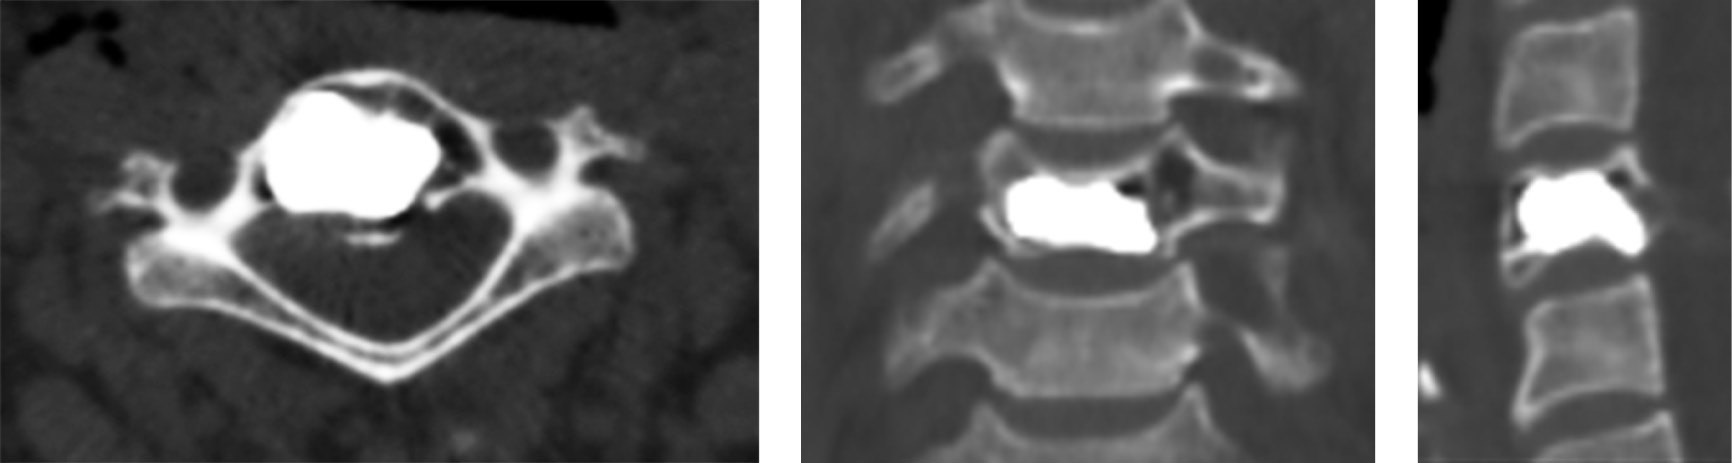

Clinical case 1. Patient A., 15 years old, presented to the advisory and diagnostic department of the Research Institute of Traumatology, Orthopedics and Neurosurgery, Saratov State Medical University, in March 2018, complaining of pain in the cervical spine radiating to the lateral surface of the shoulder girdle. The pains were persistent and intense, aggravated by head movement. The patient estimated the pain at 8 points based on the visual analogue scale (VAS). The medical history showed that the patient had been experiencing pain over the previous 6 months. A sharp increase in the pain was noted on palpation of the spinous process of vertebra C7. Using CT examination of the cervical spine, we diagnosed total aggressive hemangioma of the vertebral body C7 (Fig. 1).

Fig. 1. CT scans of vertebra C7 of patient A. before the surgery